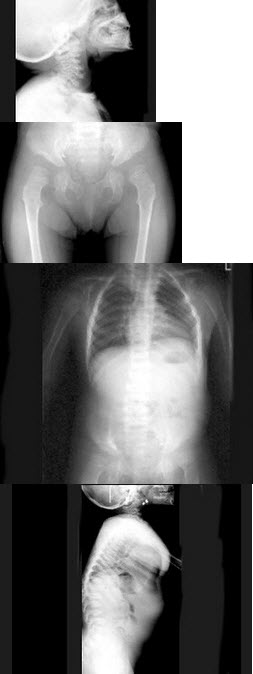

58、单项选择题

男,38岁,生活在沿海一带,腰背部疼痛半年余,根据所提供的图像,最可能诊断是()

A.石骨症

B.肾性骨病

C.氟骨症

D.成骨性转移瘤

E.骨纤维异常增殖症

141、单项选择题

女,根据其正常骨盆影像图像,判断其最可能的年龄()

A.53岁左右

B.13岁左右

C.73岁左右

D.33岁左右

E.63岁左右